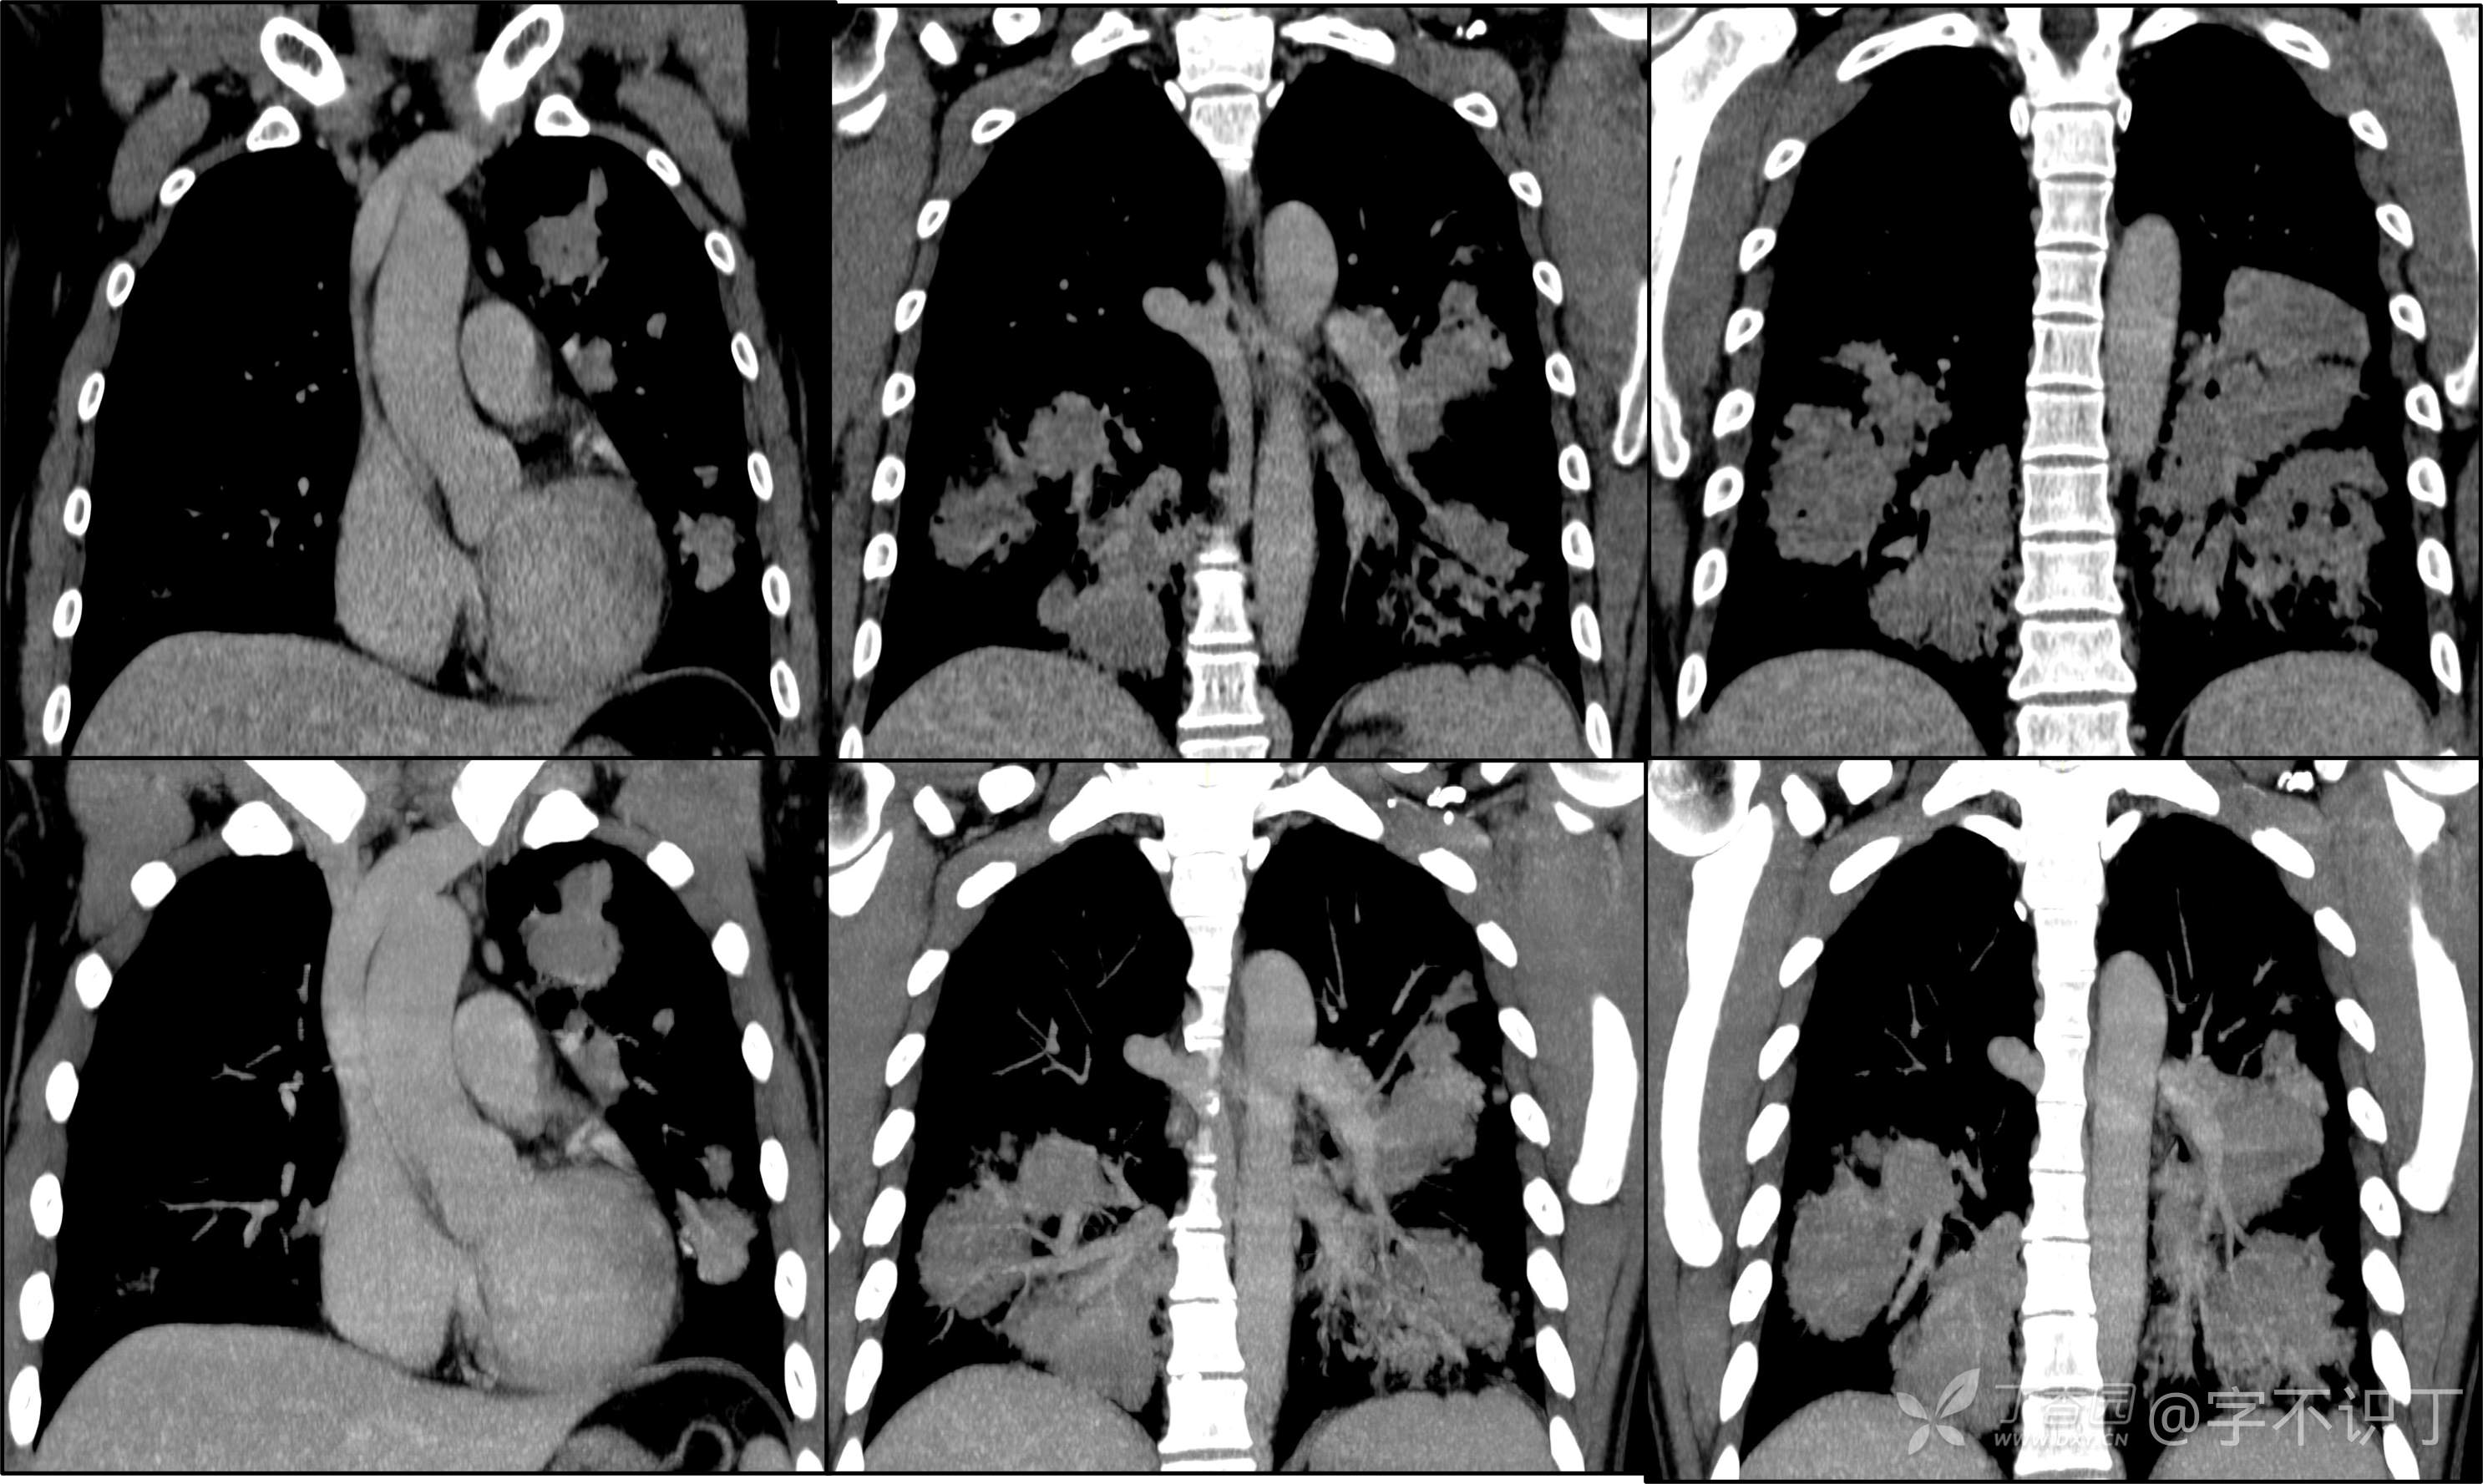

胸部病例讨论

患者性别:男

患者年龄:40岁

主诉:反复咳嗽2年,再发2月,咯血发热5天

简要病史:2年前无明显诱因出现阵发性干咳;2月前咳嗽症状较前加重,有少量白色粘液样痰,未经特殊处理,7天前咳嗽症状较前加重,伴咳黄脓样痰,痰中带血丝,予以哌拉西林舒巴坦+莫西沙星抗感染及祛痰等对症支持治疗,未觉好转,予以拉氧头孢、左氧氟沙星、布洛芬、氨溴索等对症处理,咳嗽、咳痰症状未缓解,仍有发热

体格检查:曾从事装修等工作,近半年从事煤矿管理工作。近期饮酒较频繁。既往有冶游史。

辅助检查:血液病原菌培养、分枝杆菌涂片检查、真菌涂片检查、一般细菌涂片检查、痰培养均阴性